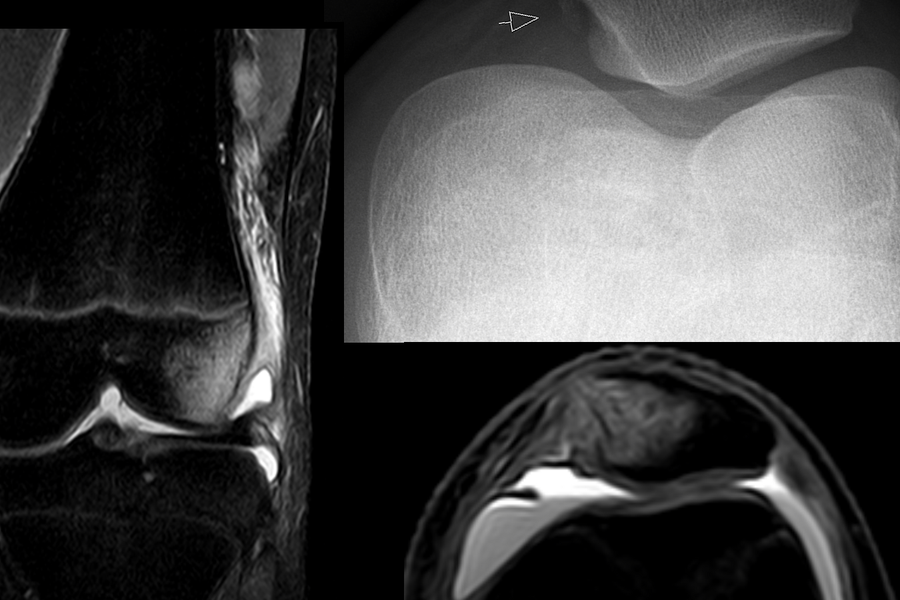

Lunate

Lunate is moon-shaped, central in the proximal carpal row, and key for wrist flexion-extension and load transfer. It ossifies in early childhood and may dislocate in high-energy injuries; chronic instability can lead to arthritis.